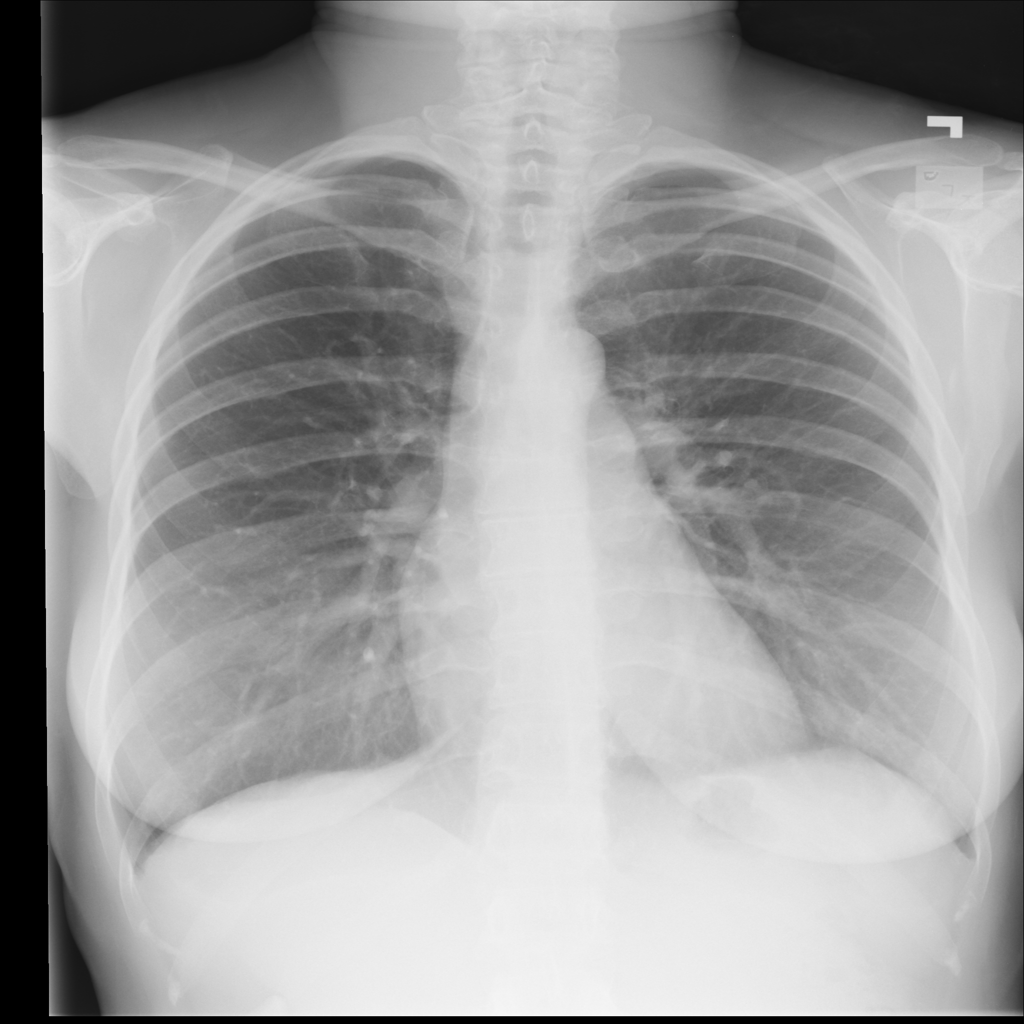

NIH Chest X-Ray dataset (Wang et al., 2017) is a large-scale medical imaging dataset comprised of 112120 X-ray images from 30805 patients. Figure 2 shows a few sample X-Ray images from the dataset. The X-ray images come labeled with up to 14 diseases and “No finding” by natural language processing (NLP) models based on the original radiological reports of each X-ray. We only select samples with “No Findings” and disease “Effusion” for the scope of our experiments. We use “Effusion” as the target label, and “Patient gender” as the sensitive attribute. After removing entries filled with N/A and abnormal values, we have a dataset with 73669 samples, and 13316 (18.1%) are labeled “Effusion”. In addition, we resized each image into size (256 * 256 * 3) with 3 channels both for computational reasons and the requirement for using pre-trained models during the training process (to be discussed in Section 6). Images are also normalized using the required mean and standard deviation based on the pre-trained model used in the experiments (Sandler et al., 2019). Detailed statistics of NIH Chest X-Ray are in Table 4.

EffusionEffusion

Total 1 0 Total

gendergender

1 7434 (10.1%) 33916 (46.0%) 41350 (56.1%56.1\%)

0 5882 (8.0%) 26437 (35.9%) 32319 (43.9%)

Total 13316 (18.1%18.1\%) 60353 (81.9%81.9\%) 73669 (100.0%)

Table 4. Statistics for NIH-Chest X-Ray dataset. EffusionEffusion is used as target label and gendergender as sensitive attribute.

Refer to caption

Figure 2. Four sample Chest X-ray images from NIH Chest X-Ray dataset.